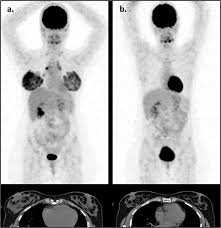

Pet Ct Scan For Breast Scanning from www.3hcare.in Pet scans are not used to screen women for breast cancer. At left is a ct scan, while the center image is from a pet scanner. A pet/ct scan is a newer technology used to create images of the body's cells as they work. The report of ct scan cannot be the basis of determining if a patient has cancer or not; Breast pet scans are known as positron emission mammography (pem). Normally, a pet scan is not used for breast cancer screening. Pet/ct, a scan that combines positron emission tomography and computerized tomography, is an extremely useful tool for determining if melanoma has spread. Its supposed to be more sensitive/specific than naf and other older scans, and comparable i think to choline or acetate (lots of studies and info on the web) and.

Bone scans, positron emission tomography (pet), and computed tomography (ct) all continue to be employed alone or in combination for the detection of breast cancers suspected to have spread. Pet/ct scans using axumin tracer, approved by fda last year and newly approved by medicare in some areas, are starting to be done at different locations. In a ct scan, you can see the broad pictures of all tissues and organs present in the body. Very subtle changes in tissue architecture are apparent on a mammogram, as are small deposits. A pet/ct scan is a newer technology used to create images of the body's cells as they work. After detecting the location of the tumor, the area will be biopsied for testing in the lab. This test can help show if the cancer has spread to your bones. At left is a ct scan, while the center image is from a pet scanner. Pet scan for breast cancer a positron emission tomography (pet) scan is an imaging test that uses a radioactive substance (called a tracer) to look for potential spread of breast cancer. A positron emission tomography scan is known as a pet scan. It can be done along with a ct scan. However, the pet scan uncovers every unusual activity in the body and is more sensitive than any other existing imaging test. Before a pet/ct scan, an iv that injects a small amount of a radioactive substance will be placed into one of your veins.

When breast cancer cancer spreads. Normally, a pet scan is not used for breast cancer screening. This substance is often called a tracer, because it helps reveal cancer in the body. The report of ct scan cannot be the basis of determining if a patient has cancer or not; At left is a ct scan, while the center image is from a pet scanner. A pet scan will help detect cancer and show how far it has spread. It is common for patients to receive a diagnosis for cancer of unknown primary. Another very common type of cancer is prostate cancer and for this type it's actually been proven that bone scans are more effective than pet scans. Am wondering if all the while we are getting ct scans for lung cancer, is this also scanning for. However, your doctor may call this a pet scan. In some cases, physicians use all three imaging techniques. Does anyone know if a ct scan can show breast cancer or colon cancer rather than the standard mammogram or colonoscopy? It's an effective imaging test for finding cancer and learning its stage.